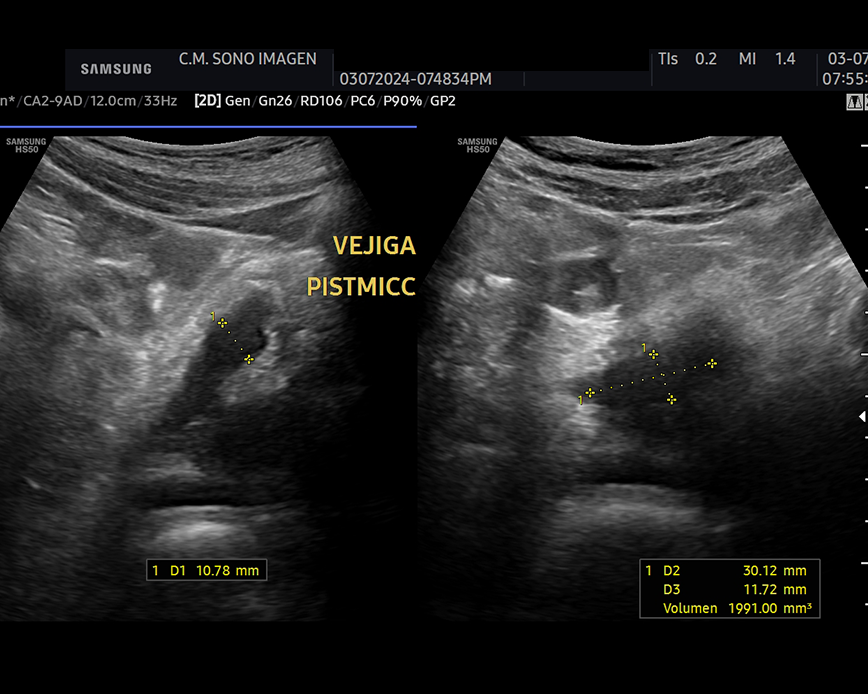

Ecografía Prostática

- hiperplasia prostática benigna(HPB)

- dificultad para orinar o retención urinaria